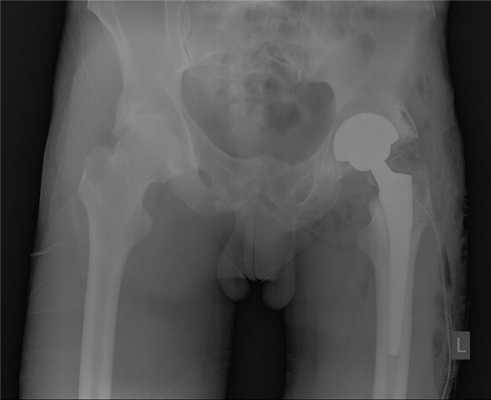

Пациент К. 68 лет, на протяжении 1 года отмечал постепенное нарастание болей и ограничение амплитуды движений в правом тазобедренном суставе. Обратился в К+31 в августе 2017 года, при выполнении рентгенографии выявлен асептический некроз головки правого бедра, коксартроз 3 стадии.

Выполнено тотальное эндопротезирование правого тазобедренного сустава эндопротезом фирмы Zimmer бесцементной фиксации, пара трения керамика\полиэтилен. Гладкое течение послеоперационного периода.

Рентгеногграммы после операции, положение компонентов эндопротеза правильное. Пациент активизирован на следующий день после операции, обучен ходьбе с дополнительной опорой на ходунки. Вторые сутки после операции, пациент ходит по палате и коридору без посторонней помощи с дополнительной опорой на ходунки.

Пациент выписан на 4 сутки после операции в удовлетворительном состоянии. В настоящее время функция опоры и ходьбы полностью восстановлена, ходит без дополнительной опоры, боли не беспокоят, восстановился нормальный стереотип походки.